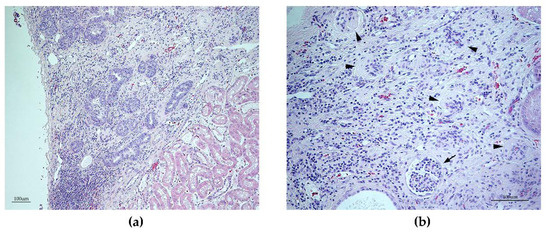

3.6. Histopathology Findings

3.7. Characterization of Canine TTC8 Transcripts in the Retina